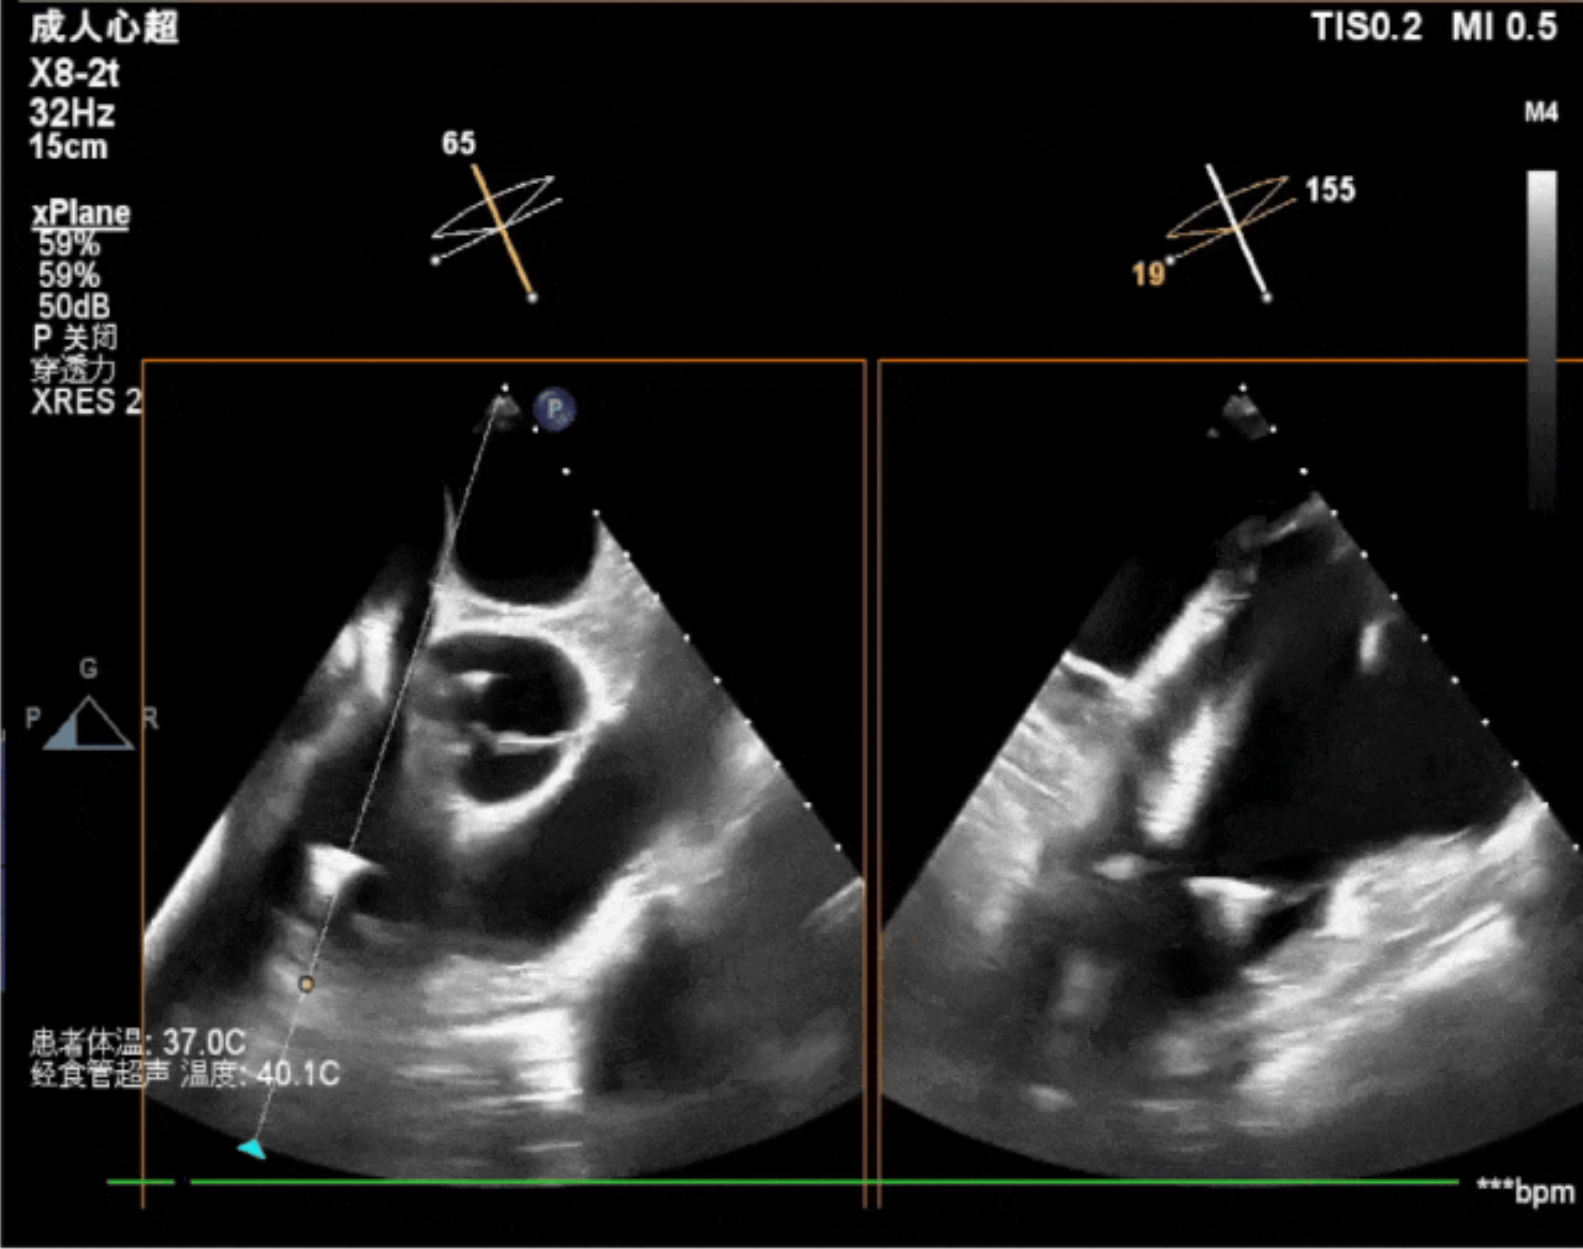

術(shù)中經(jīng)食道超聲輔助下可見(jiàn)LuX-Valve Plus夾持件抓捕瓣葉狀態(tài)良好,夾持件在位,室間隔錨定位置良好,假體瓣膜整體錨定狀態(tài)穩(wěn)固。

術(shù)后即刻經(jīng)食道超聲可見(jiàn),三尖瓣假體瓣膜位置合適,牛心包瓣葉運(yùn)動(dòng)狀態(tài)良好,開(kāi)閉正常,瓣周及瓣葉對(duì)合緣處未見(jiàn)明顯返流,心電圖及心包狀態(tài)較術(shù)前無(wú)明顯變化。

本次直播手術(shù)中,手術(shù)團(tuán)隊(duì)在超聲與DSA等多維影像手段的支持下,精準(zhǔn)嫻熟的完成LuX-Valve Plus瓣膜的植入,器械操作時(shí)間僅為30分鐘,瓣膜植入后術(shù)中即刻三尖瓣返流消失,多普勒超聲下無(wú)明顯瓣周漏或中心性返流,肺動(dòng)脈壓正常,平均跨瓣壓差僅為1mmHg,人工瓣膜運(yùn)動(dòng)正常,術(shù)后1小時(shí)內(nèi)該患者即安返病房。